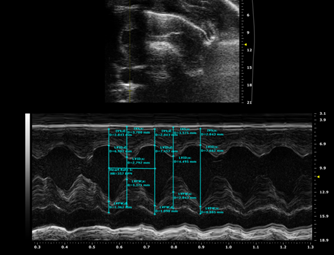

观察指标:心脏B超检测 EF及左心室舒张末内径(LVEDD)和左室收缩末内径(LVESD);Masson染色或天狼星红染色观察心肌组织纤维化情况,伊文思蓝-TTC染色观察梗死面积;HE染色观察病理;ELISA检测血清中的TNF-α、IL-1β及IL-6等炎症因子。

图注:TAC造模前心电图

图注:TAC模型心电图

图注:模型前正常SD大鼠B超图

图注:TAC模型4周后心电图